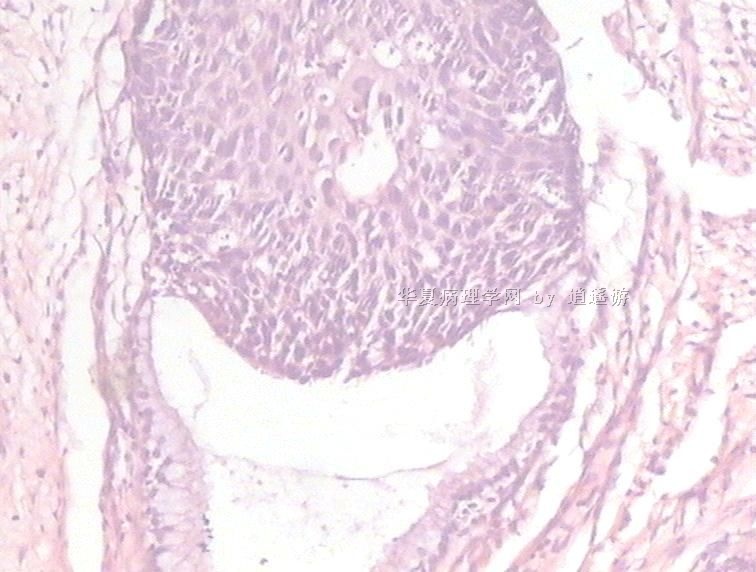

姓    名: ××× 性别:  女 年龄:  40

标本名称:  宫颈leep环切术切除组织

简要病史:  宫颈Ⅲ度糜烂

图1、2,10×,图3-6,4×,图7、8,40×

设备不够好,图像较模糊。

CIN3级累腺。

多看看是否有浸润,以及切缘。

CIN3级累腺,切缘是否干净?

CIN3级累腺

未见到浸润,但边缘看起来未切净。

同意.

很典型的.